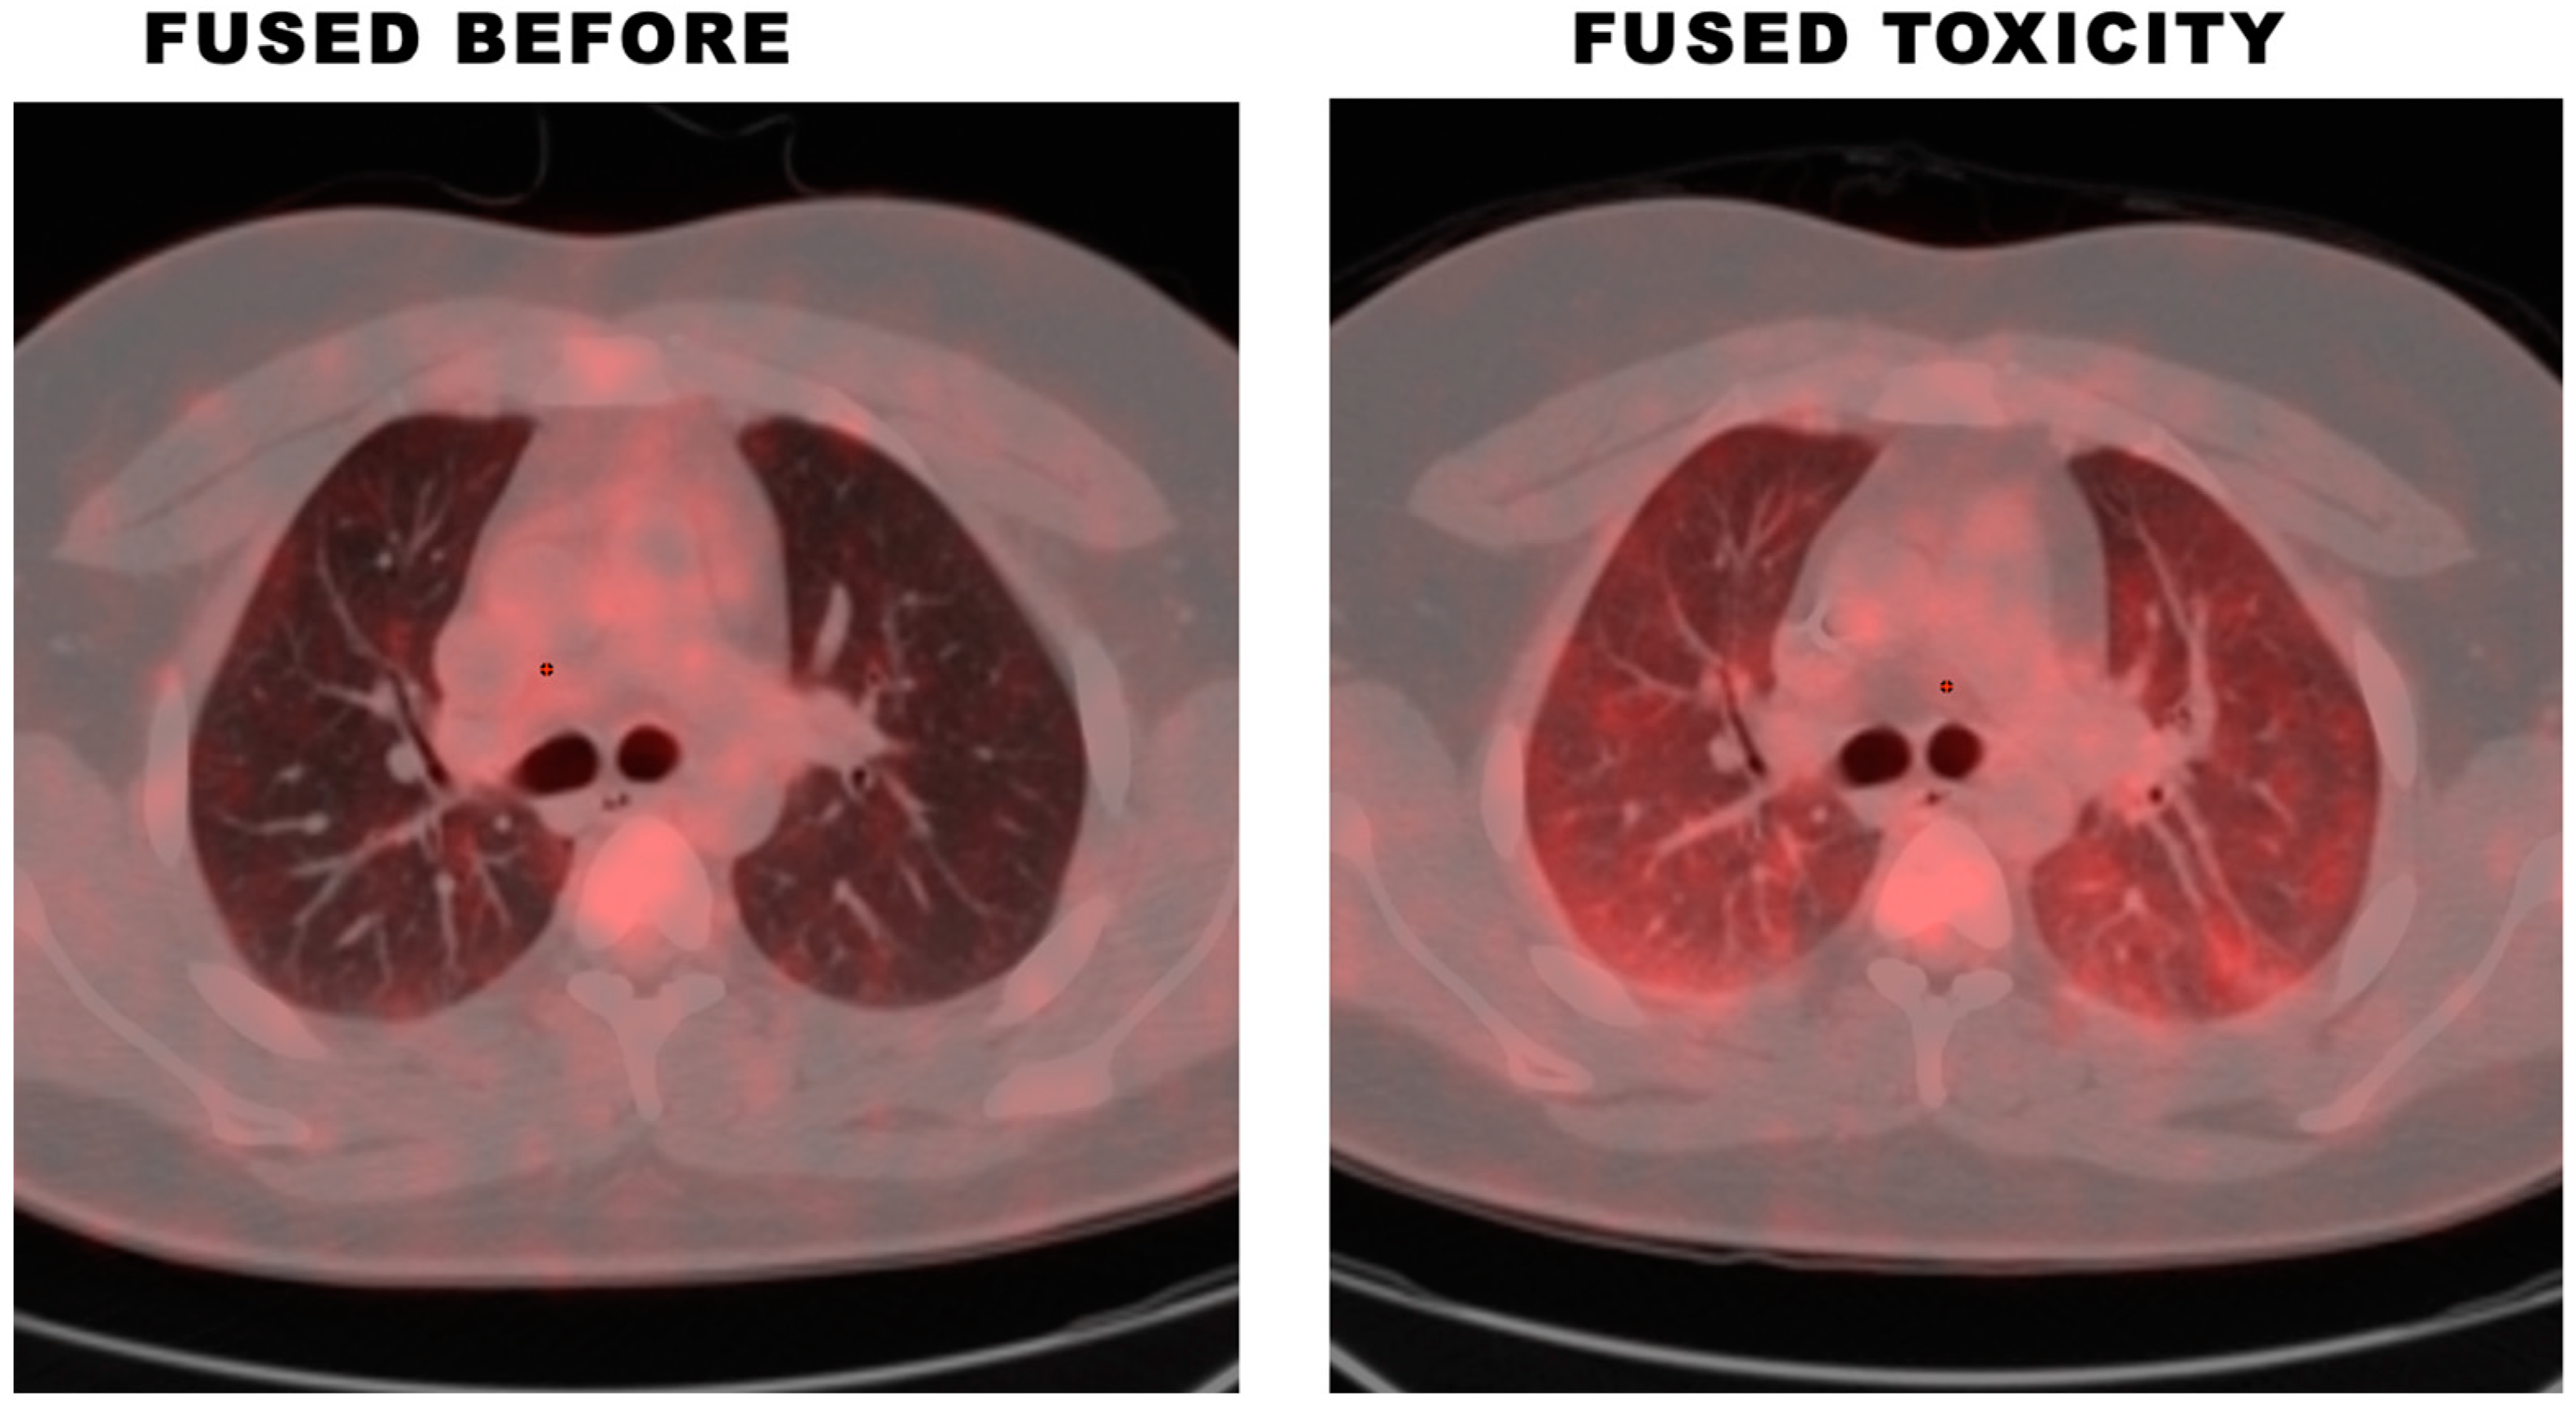

2.1. Cohort 1—Clinical BPT and 18F-FDG PET/CT Findings

| Mean SUVmax of Lungs | 0.86 (CI 0.4–1.9) | 2.66 (CI 1.8–3.7) |